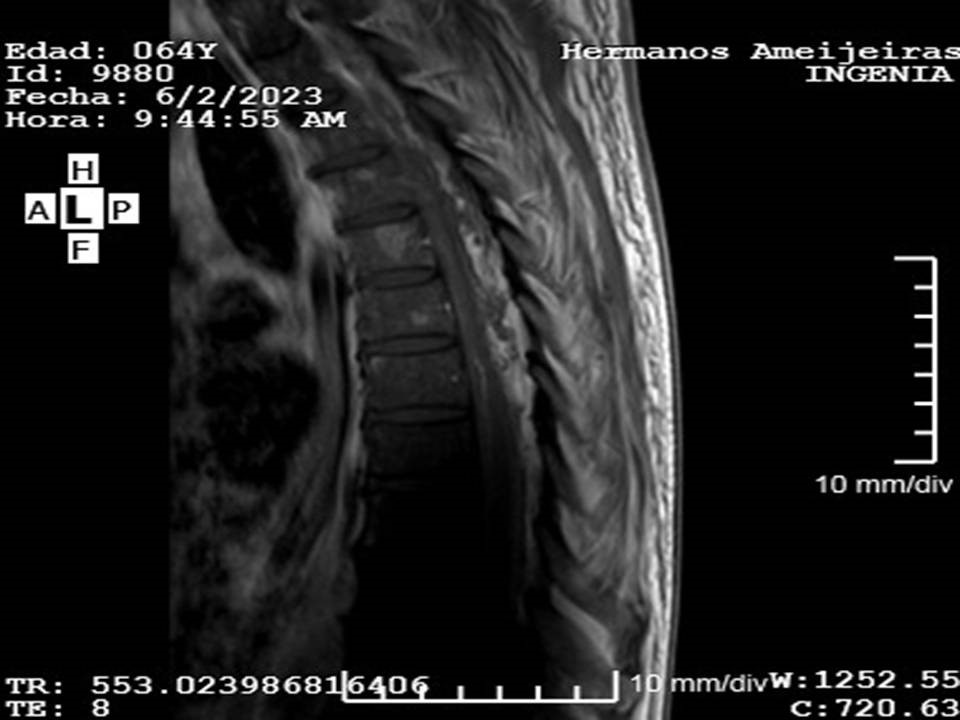

La Figura 1 muestra las imágenes de la resonancia magnética nuclear con gadolinio de columna dorsal y lumbosacra. Se observa la presencia de una imagen ovalada compleja, que se extiende desde T5 hasta el tercio superior de T7, con desplazamiento de la pared lateral izquierda de la médula, con una longitud de 68 mm, compatible con un absceso epidural espinal (Figura 1a). A nivel del músculo psoas derecho se observa colección que mide 12 cm, compatible con un absceso (Figura 1b).

A)

B)

Figura 1. Resonancia magnética nuclear 3 Tesla con gadolinio de columna dorsal y lumbosacra: a) corte sagital, secuencia T1, se observa imagen ovalada compleja compatible con absceso epidural espinal, extendido desde T5 hasta el 1/3 superior de T7; b) corte sagital, secuencia T2, a nivel del músculo psoas derecho se observa colección compatible con absceso.